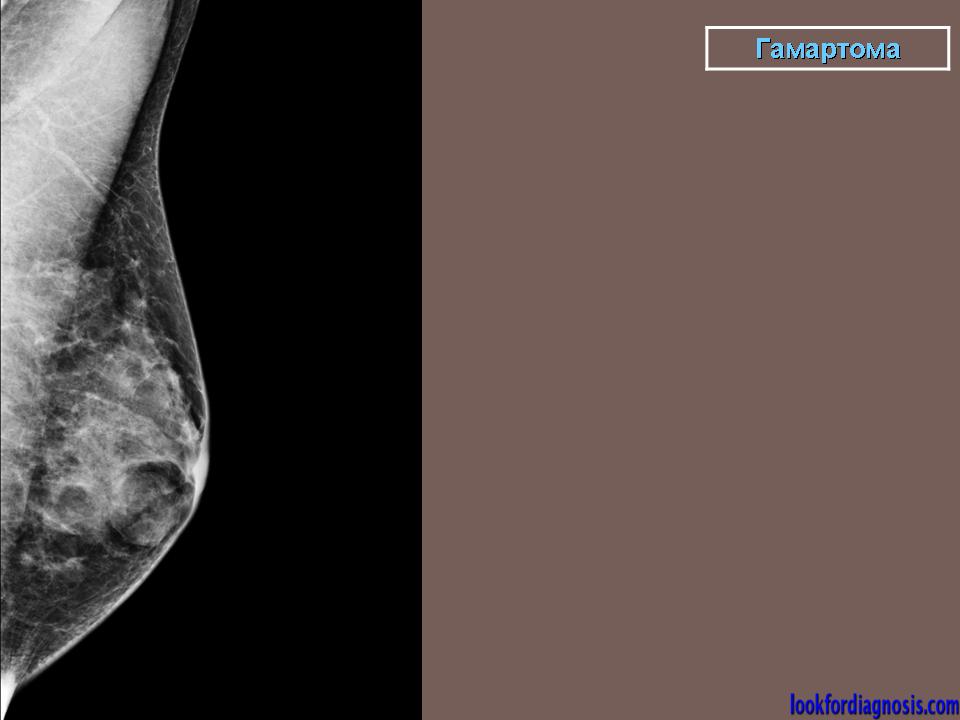

Гамартомы молочных желез.

Приложения:

0.gamartoma.png0.gamartoma_1.jpg0.gamartoma_1.png0.gamartoma_11.jpg0.gamartoma_12.jpg0.gamartoma_13.jpg0.gamartoma_14.jpg0.gamartoma_141.jpg0.gamartoma_15.jpg0.gamartoma_16.jpg0.gamartoma_21.jpg0.gamartoma_24.jpg